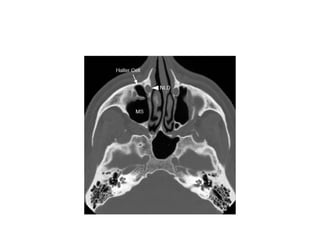

Haller cells

• Ethmoidal air cells belonging to the

anterior ethmoidal group.

• Also known as the infra orbital cells

• Adhere to roof of maxillary sinus forming

the lat wall of infundibulum

• Enlargement of these cells can impede

the maxillary sinus drainage

Haller Cell

Septae